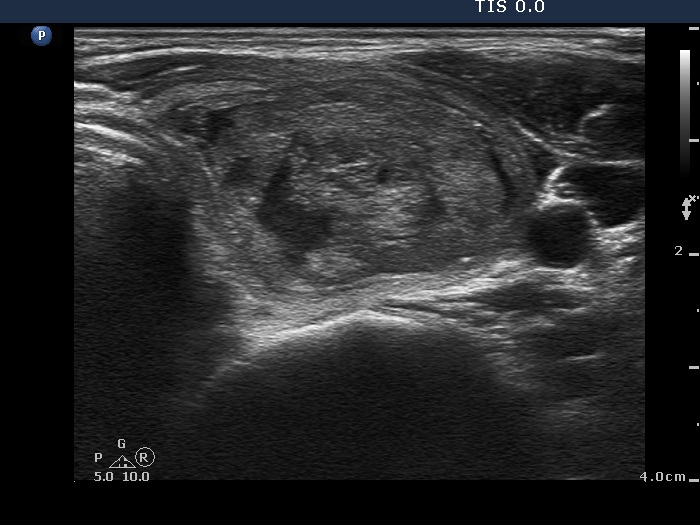

Third session of therapy (ultrasonographic picture 1)

Right lobe, horizontal scan. The nodule decreased in size and is composed of amorphous material.